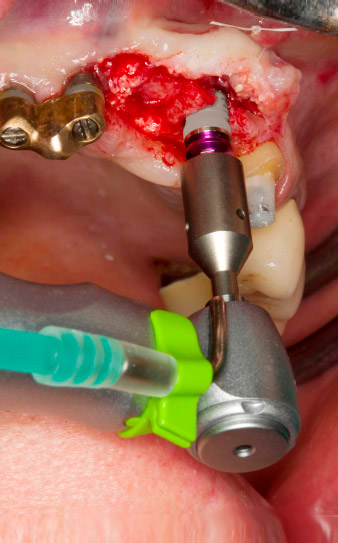

El hueso alveolar de la posición 22 resultó tener unas dimensiones suficientes. Las figuras 2 y 4 muestran la preparación del lecho del implante, el corte de rosca y la colocación del implante con el equipo Implantmed.

El nuevo motor para implantología se utilizó siempre con los contra-ángulos quirúrgicos adecuados de W&H.